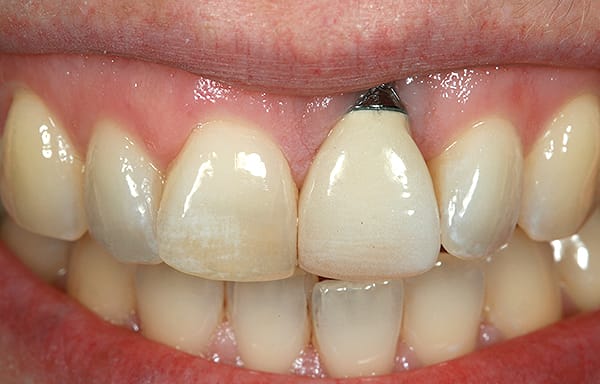

A young woman presented with a midfacial recession defect of roughly 4 mm to the junction of the abutment-implant interface (Figure 1) that was also present in her smile (Figure 2). She had previously consulted several surgeons who were hesitant to treat her because of the defect and high smile line. A cosmetic dentist subsequently referred her to the authors.

Before a clinician can decide on treatment, a diagnosis must be made whether the implant is healthy or not, meaning normal bone levels around the implant. Another decision of concern was whether to retain the dental implant. It was determined that the implant was healthy, however the recession defect was due to an overcontoured custom abutment secondary to excessive facial implant angulation (Figure 3). The tendency for most surgeons when presented with such a recession defect is to think of a “root” coverage type surgical procedure. Patients with a thin or intermediate phenotype may not respond well to such a technique. It was also mentioned previously that an exposed implant abutment is absent of blood supply and may be contaminated with endotoxins that would constrain the predictability of healing with a coronal positioned connective tissue flap. One of the tactics to predictably ensure primary flap closure of the defect is to “decoronate” or bury the implant12,13 by removing the existing implant abutment and placing a surgical cover screw (Figure 4). Consequently, the soft tissues will heal and cover the head of the implant—“nature’s connective tissue graft” or spontaneous in-situ gingival augmentation. A resin-bonded–retained bridge was used as a provisional transitional restoration (Figure 5 and Figure 6). After a 2-week period, closure of the tissue was evident but de-epithelialization was required to ensure completion (Figure 7). Three-months post-ridge healing, sounding to the implant head with a periodontal probe revealed 5 mm of coronal soft tissue thickness (Figure 8). It was then decided that a secondary ridge augmentation procedure was not necessary, only second-stage implant uncovering surgery was needed with a crestal incision biased toward the palate. The shape of the patient’s pre-existing abutment was modified creating a flat facial contour, disinfected, and replaced as a provisional abutment (Figure 9). The original crown was also used as a temporary following an acrylic reline (Figure 10). After 1-month post-implant exposure, a new acrylic provisional restoration was fabricated and used to re-shape and sculpt the soft tissues to match those of the contralateral natural tooth14 (Figure 11). The flat contour concept of the abutment restoration is followed throughout the definitive abutment (Figure 12) and crown restoration (Figure 13 and Figure 14). Figures 15 and 16 show the intraoral and smile view of this patient, respectively, receiving remedial treatment at 5-years post-surgical treatment.